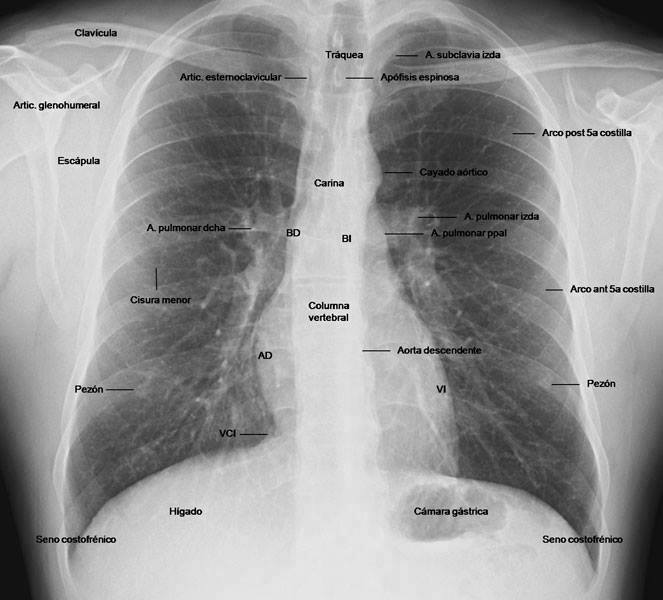

El que tot mèdic ha de saber: la radiografia de tòrax